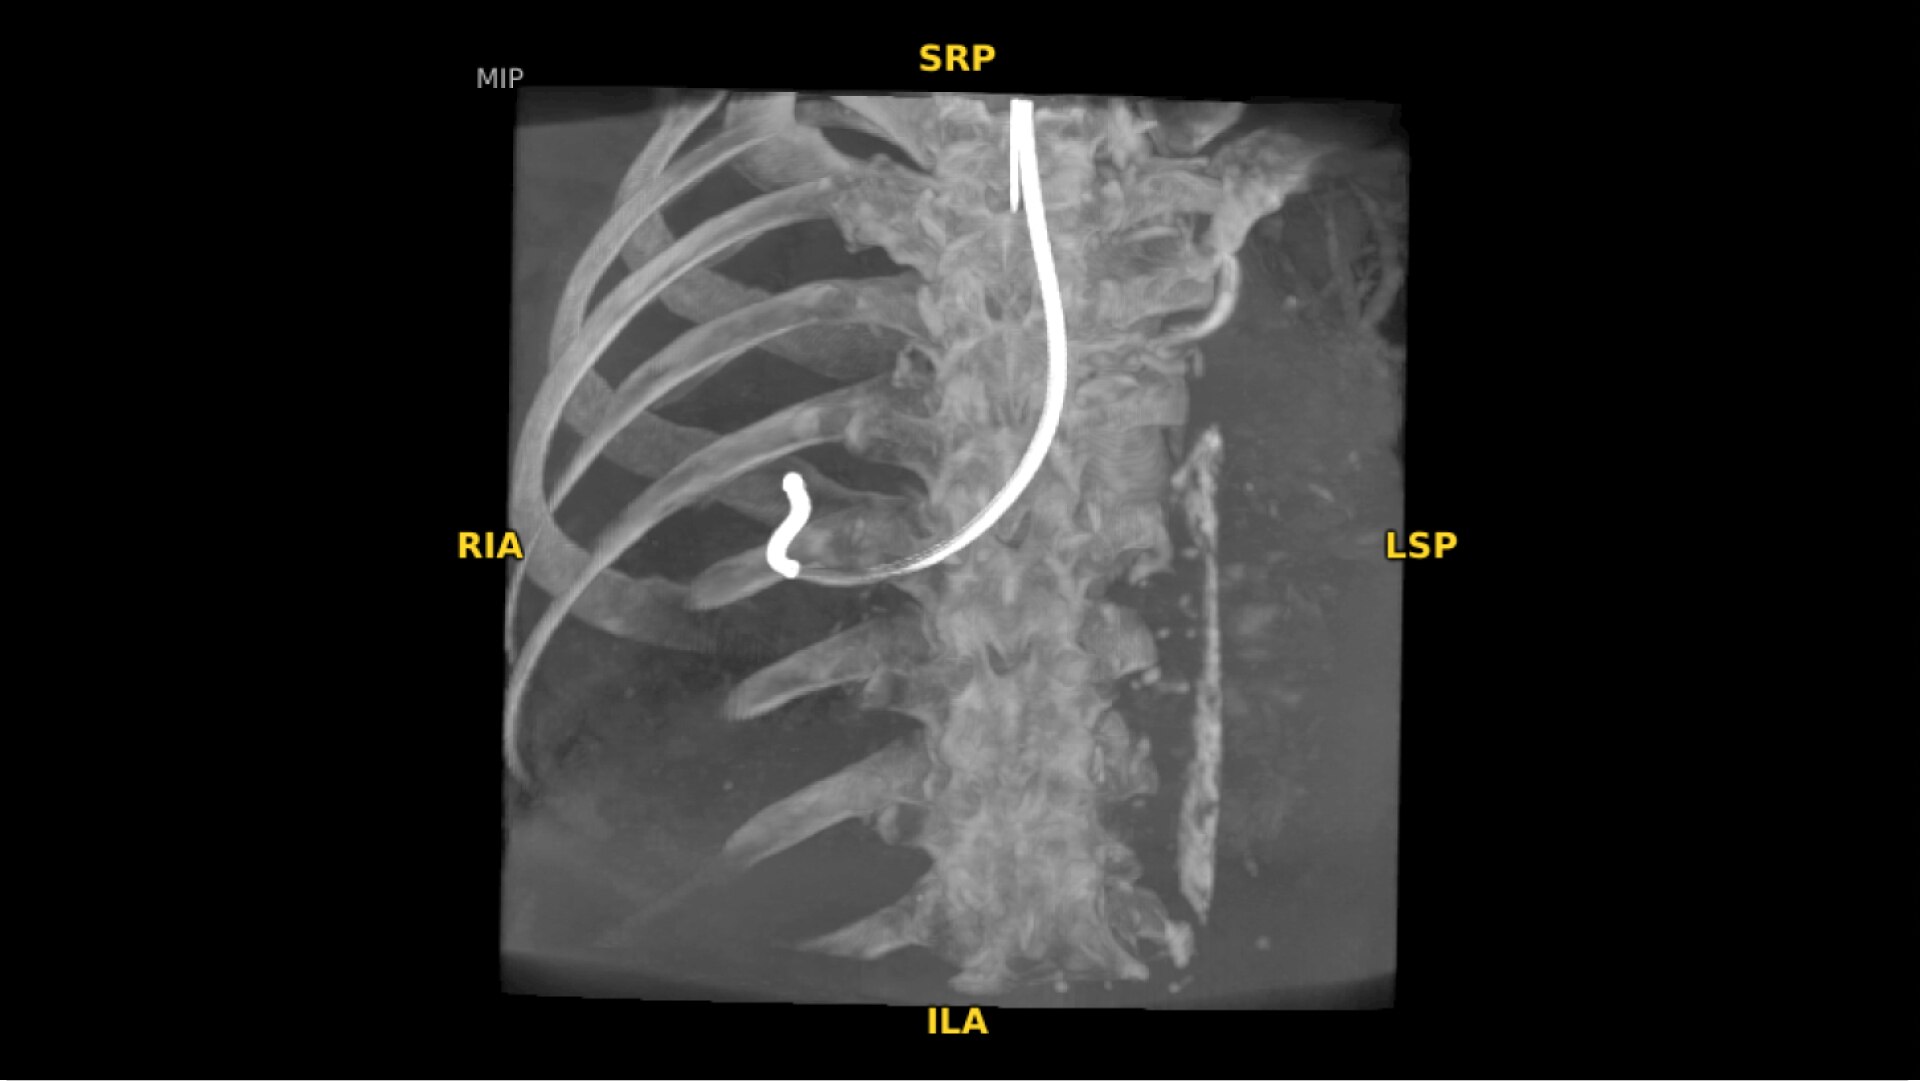

19 cm3 CT-like images presented intraoperatively in minutes

See more levels during a spinal fusion, or more of the pelvis or femur during an orthopedic procedure. With a 19 cm x 19 cm x 19 cm volume, OEC 3D captures a 67% greater volume than other 3D C-arms*.

Enhance intraoperative decision-making with visualization capabilities of Augmented Fluoroscopy in the OEC 3D Volume Viewer. Analyze five perspectives with 3D imaging tools including Multi-Oblique Mode, scrolling 512 slices, zoom, and more.